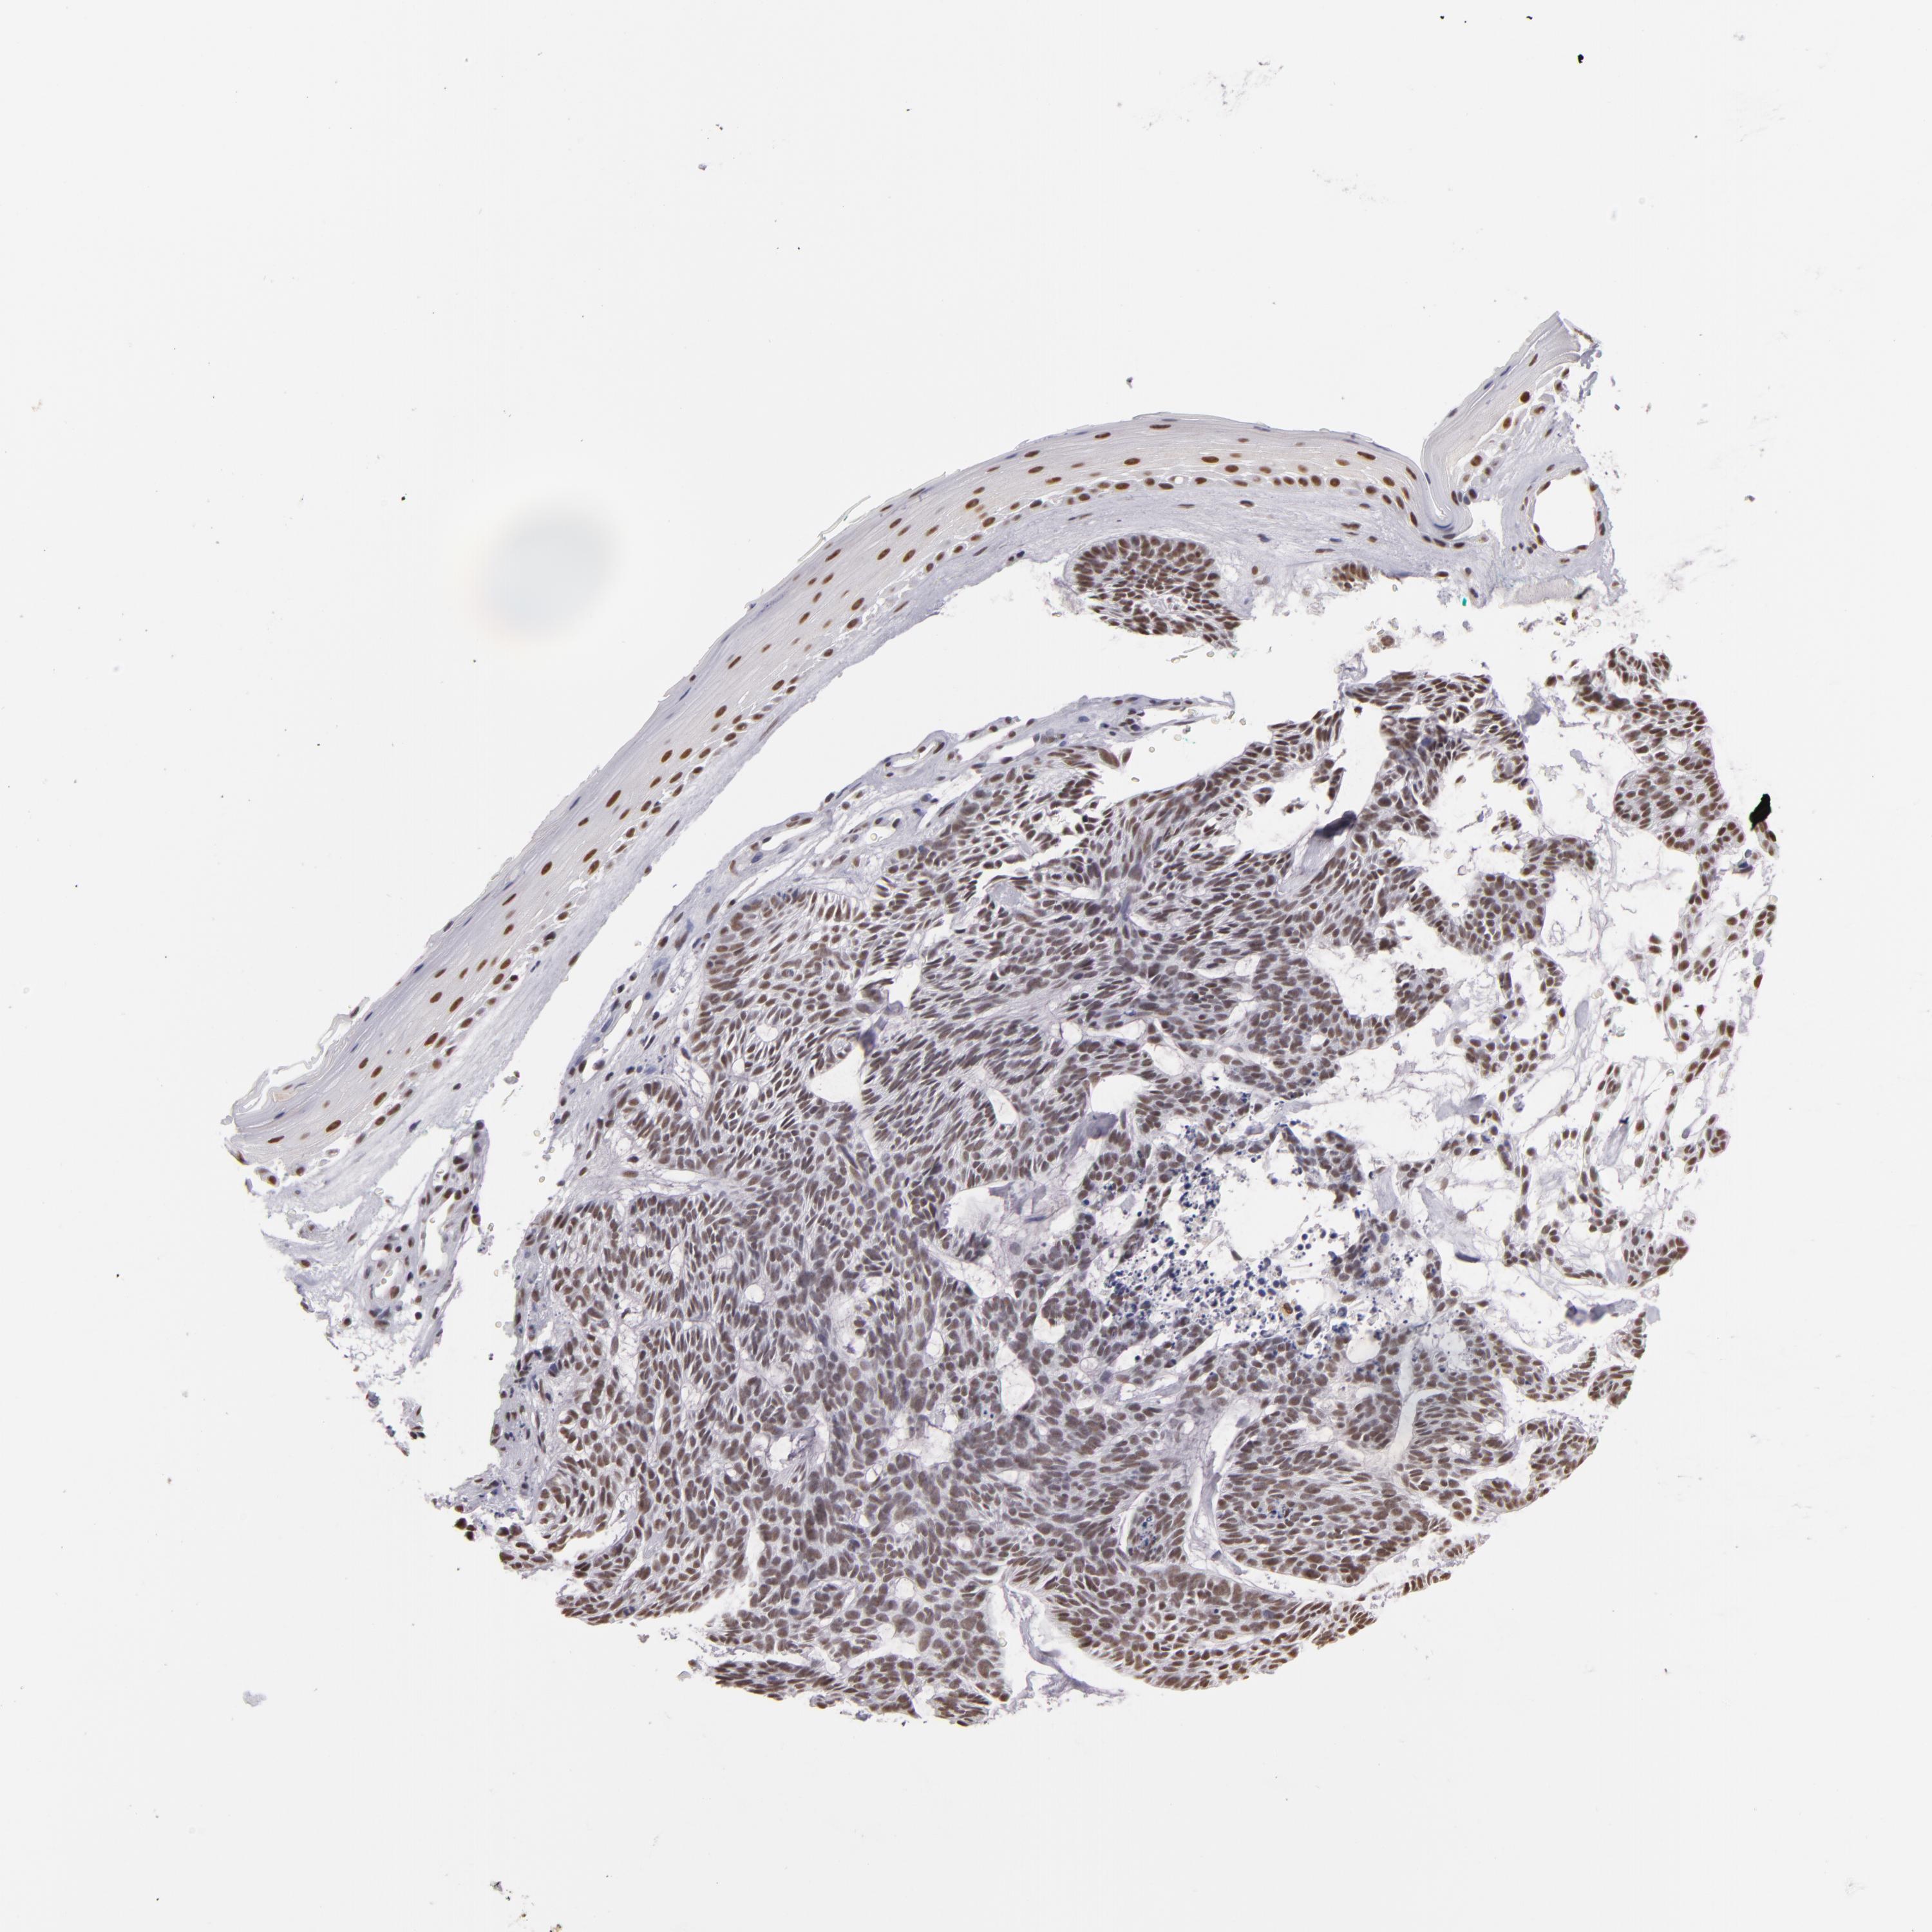

SKIN CANCER - Protein expressioni

A mouse-over function shows sample information and annotation data. Click on an image to view it in a full screen mode. Samples can be filtered based on level of antibody staining by selecting one or several of the following categories: high, medium, low and not detected. The assay and annotation is described here.

Antibody staining in the annotated cell types in the current human tissue is reported as not detected, low, medium, or high, based on conventional immunohistochemistry profiling in selected tissues. This score is based on the combination of the staining intensity and fraction of stained cells.

Each image is clickable and will lead to virtual microscopy that enables deeper exploration of all samples and also displays staining intensity scores, fraction scores and subcellular localization as well as patient and tissue information for each sample.

Antibody HPA001552

Antibody HPA001846

Staining

Low

Intensity

Weak

Location

Nuclear

Basal cell carcinoma